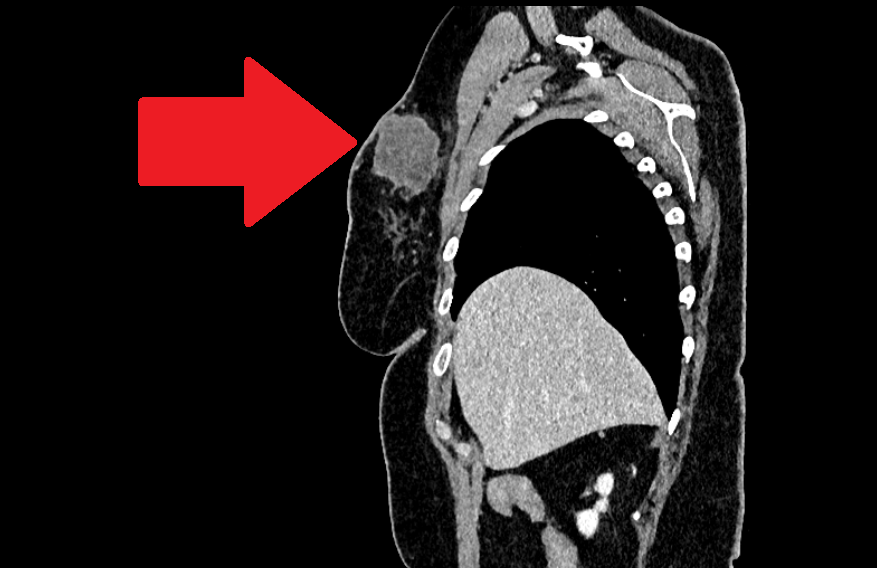

Опухоль правой молочной железы. Компьютерная томография с контрастированием. Боковая проекция

В этот же день была проведена компьютерная томография органов грудной клетки, брюшной полости, забрюшинного пространства и малого таза с внутривенным контрастированием, к сожалению, кроме опухоли и подмышечных лимфоузлов, выявлены метастатические очаги в легких: